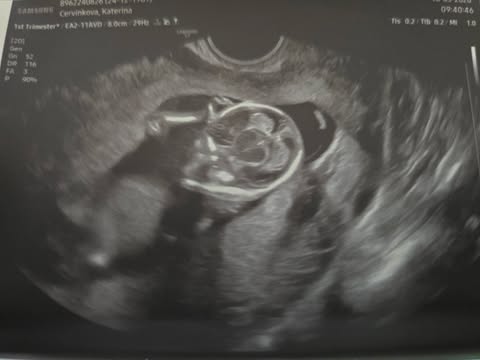

Děložní čípek a rané těhotenství

Dobrý den, mam dotaz, pro nekoho mozna hloupy ale rada bych znala vase názory. Dnes jsem mela dostat menstruaci (17.3.), většinou ji dostanu hned ráno, dnes rano ale vůbec nic, uz je odpoledne. Bývám unavená cca posledních 5 dní, chodím častěji na malou, pobolivaji me prsa po stranách jako u paží, jsou těžká, a zvětšená, bazální teplota se mi pohybuje kolem 37 a 37,1. Děložní čípek mam poměrně vysoko neni ani tvrdý ani měkký a je uzavřený. A 15.3. jsem cítila krátce takové píchání a tahání u stydké kosti, cca 3 minuty a pak to přestalo. Doma mam test od dr.max ale zatim mi to nepřijde podstatné se testovat. Budu vděčná za každou radu, děkuj